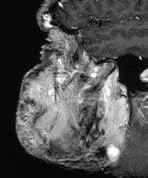

There is an enormous facial angioma extending through the palate to almost obliterate the oro-pharyngeal airway. A small extension into the middle cranial fossa from the infra temporal fossa is shown. Signal change is present in the immediately overlying brain suggesting a breach in the dura. Bone is partly destroyed in and around the right orbit, especially the right frontal bone.